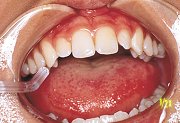

開口障害を主訴とした11歳の女子中学生。無痛的最大開口量は25mmであった。遠隔地からの来院であり、初診日に に装着するスプリントを直接法により製作した。 |